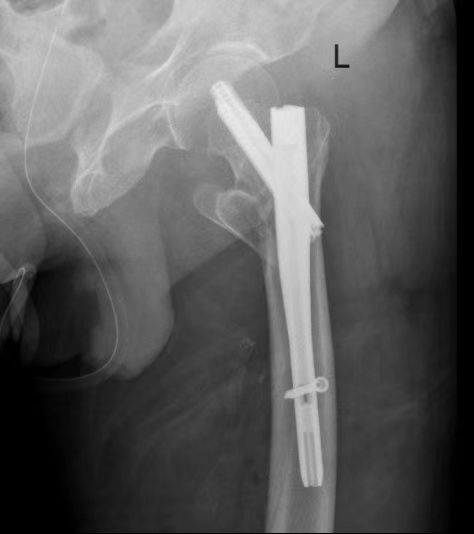

ICU与呼吸内科团队确保患者拔管后呼吸功能稳定;心血管内科、内分泌科精准调控血压、血糖至精准范围;神经内科评估患者脑梗后状态。手术麻醉科量身定制创伤最小、最稳定的个性化麻醉与监测方案,严阵以待可能出现的循环和呼吸波动。在此基础上,骨科团队最终决定采用微创的“闭合复位髓内钉内固定术”,力求以最短时间、最小创伤完成固定。

在万全准备下,手术如期展开。术中,多学科团队配合默契,操作精准流畅。仅用时40分钟便成功完成骨折复位与固定,术中出血极少,患者生命体征平稳。这场高风险手术取得了关键性胜利。